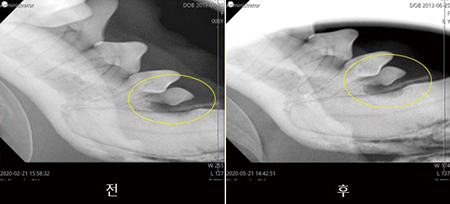

2) Emdogain의 적용증례

▷ 달콩이(8살 시츄. 55.5kg/부정교합 심한 상태)

- RL/LL 견치 후방 치조골 소실

- RL/LL 엠도게인 진행(2020.02.21)

술 후 3개월 재진

- 견치 후방,pm1 뿌리쪽 치조골이 차 오름[fig 07].